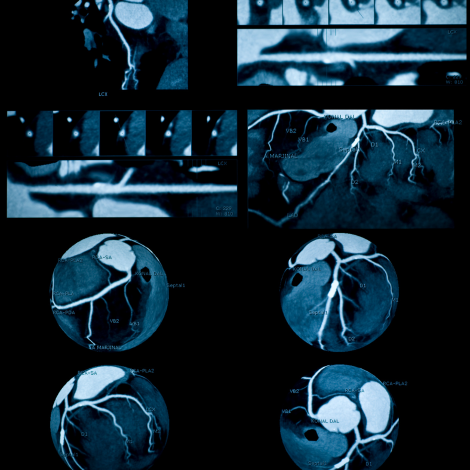

Angiography / Venography MRI

MRI angiography is a specialised tests used to study the blood flow in the arteries (vessels carrying pure blood). The following body parts are usually recommended for MR angiogram: Brain; Neck; Heart; Arms and hands; Chest; Abdomen; Pelvis; Legs and feet. This is to evaluate for any blockage, aneurysms or vascular malformations etc.MRI venography is a specialised tests used to study the blood flow in the veins (vessels carrying impure blood). This is to evaluate for any blockage, thrombosis, varicose veins and vascular malformations.